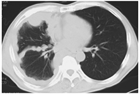

1. TNM分類の第9版の改訂では、T因子が大きく変更され、胸膜肥厚のCT計測値が採用されている。2025年の中皮腫ガイドラインでは、採用論文のすべてに第8版TNM分類が使われているので、本改訂では必要に応じてTNM分類のversionを併記し、また第8版、第9版TNM分類およびそれらのもとになったIMIG分類の対比を表で示した。

1. 胸膜中皮腫は壁側胸膜の中皮細胞に初発する難治性腫瘍であり、石綿(アスベスト)曝露と密接に関連して発生する。